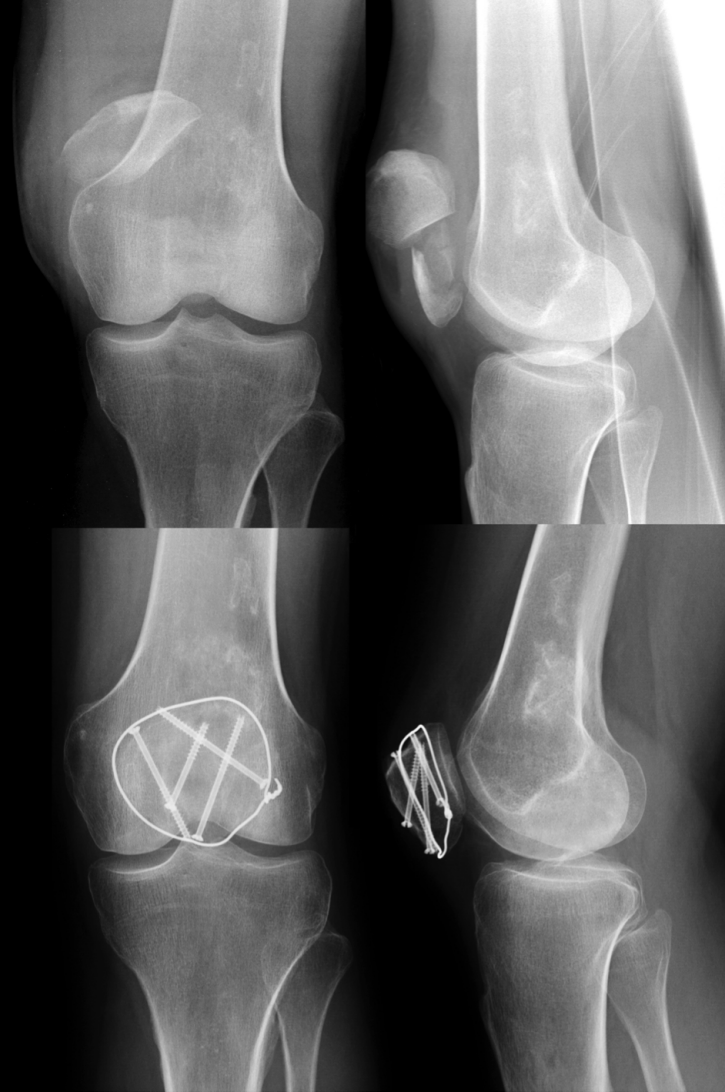

螺钉固定可通过纵向稳定骨折端降低因张力带松弛导致骨折块移位的风险(图4)。螺钉应垂直于骨折线植入,且直径需与髌骨尺寸匹配(如3.5mm皮质骨螺钉)。对于较小的碎骨块,可使用2.4mm或2.0mm的辅助螺钉根据骨块大小进行复位固定。若采用拉力螺钉固定骨折,需额外加用环形环扎钢丝(传统不锈钢丝或编织缝线)增强固定。Thelen等通过生物力学分析证实,空心螺钉联合前侧张力带固定的抗骨折移位能力显著优于传统前侧张力带固定。

图4:髌骨粉碎性骨折术前X线片(上图)。术后3个月采用螺钉联合张力带固定(下图)